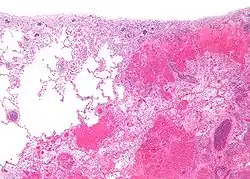

Micrograph of a pulmonary infarct (right of image) beside relatively normal lung (left of image). H&E stain.

Infarction of the lung due to a pulmonary embolism